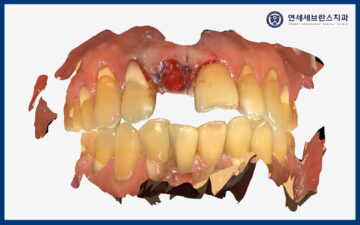

육안으로 확인 시 앞니가 부러져서

뿌리만 남아있던 상황이었습니다.

그리고 부러진 치아의 옆 치아는

많이 흔들리는 상황이고,

환자분께서 아래로

내려온 것 같다고 하셨습니다.

또한 CT를 촬영하여 확인해 보니,

왼쪽 위 치아는 치조골 골절을

관찰할 수 있었습니다.